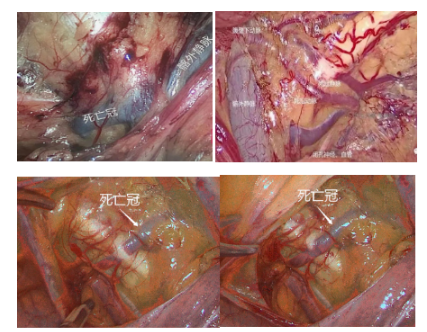

1、髂耻韧带外侧紧邻髂外动静脉,且分支各异,尤其注意避开“死亡冠”血管。

“死亡冠血管”:髂外动静脉与髂内动静脉之间的交通支,垂直行走在髂耻韧带表面,属于变异的闭孔血管,一旦损伤,出血凶猛。